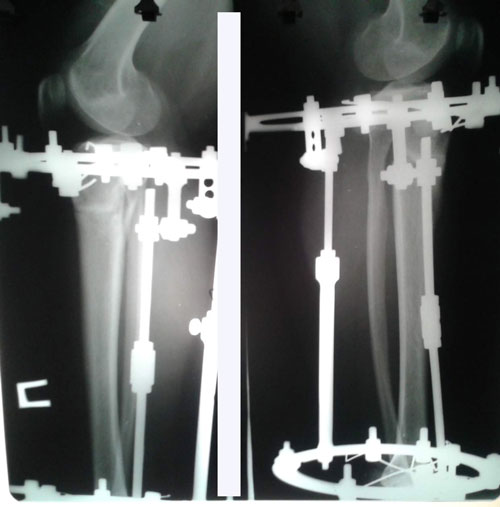

Ножки супер! разрешено всё без ограничений, все нагрузки: спорт, фитнес, каблуки любых размеров - Вам очень они пойдут! Нельзя: беременеть в течении первых 6 месяцев с момента снятия аппаратов!

Не забывайте про наш форум, высылайте фото ножек, пишите отзывы, нам это важно, это наша работа - искусство, которым мы гордимся!

Вам, счастья, любви и всех благ!